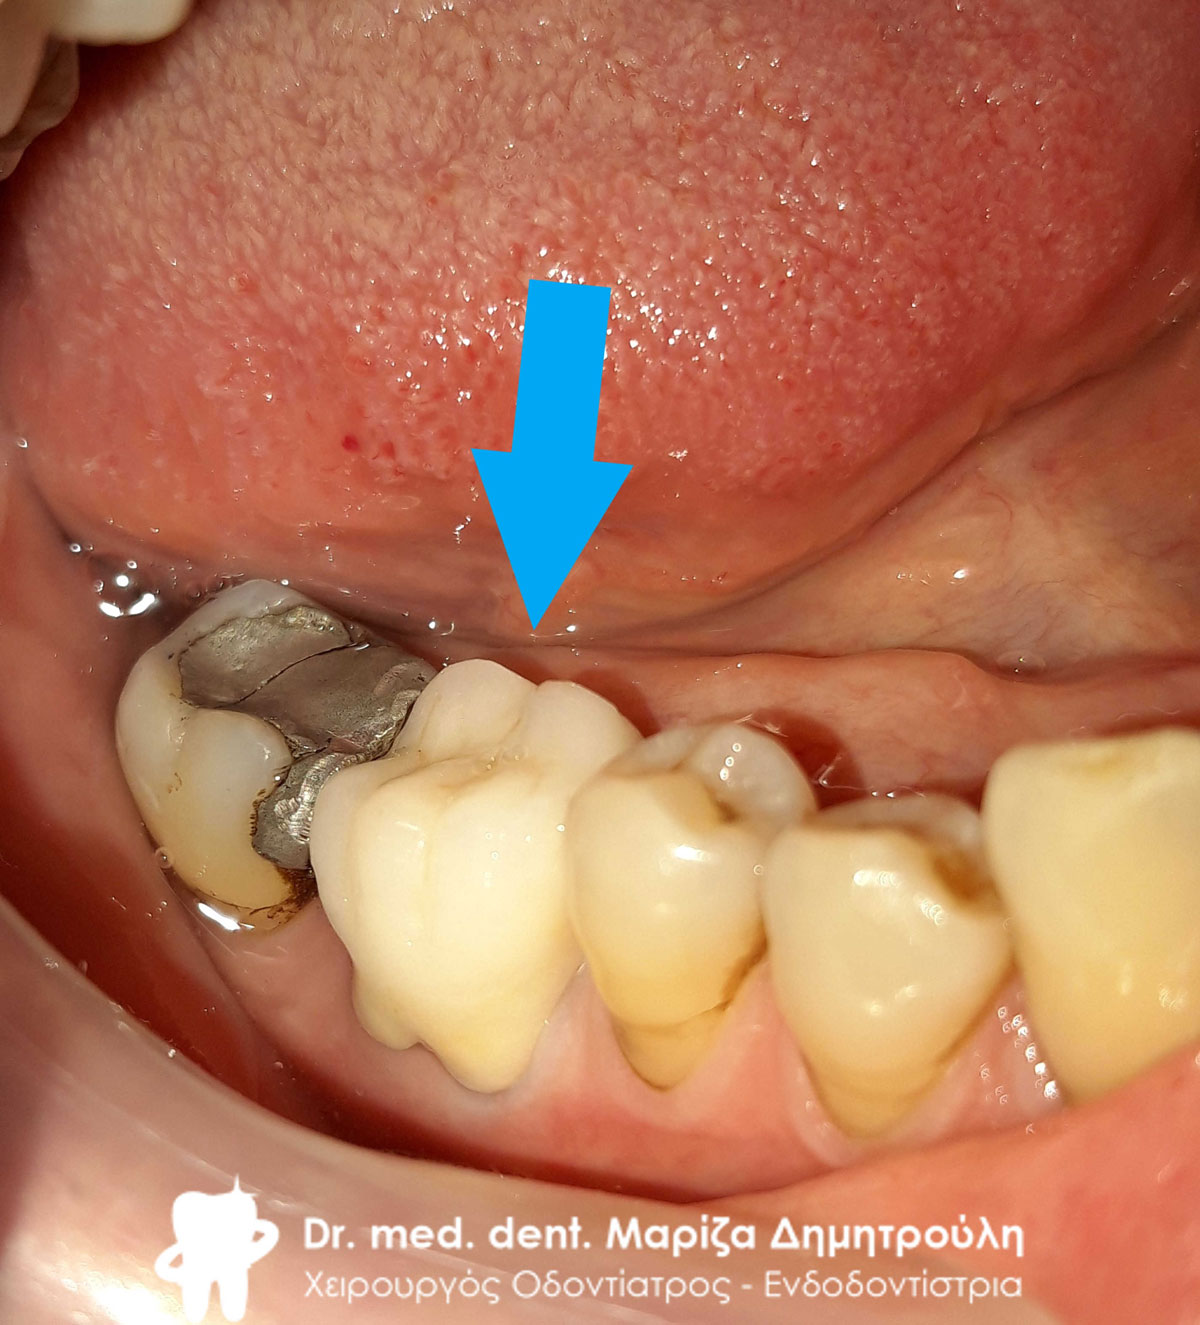

Περιστατικό – Ολοκεραμική στεφάνη / θήκη ζιρκονίου στην αριστερή πλευρά της κάτω γνάθου

Η ασθενής είχε ένα παλιό μαύρο σφράγισμα αμαλγάματος το οποίο την πονούσε. Μετά την κλινική και ακτινογραφική εξέταση του δοντιού αποφασίστηκε η αφαίρεση του παλιού σφραγίσματος, η νέα ανασύσταση και η κάλυψη του δοντιού με ολοκεραμική θήκη δοντιού, καθώς το οδοντικό έλλειμμα ήταν μεγάλο.

Αρχική κλινική εικόνα του δοντιού με το παλιό μαύρο σφράγισμα αμαλγάματος

Τελική εικόνα του δοντιού με τη νέα ολοκεραμική στεφάνη